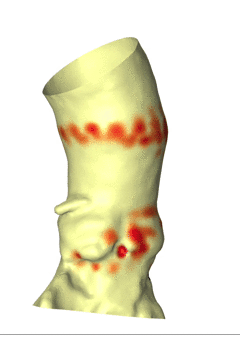

FEops评估冠脉风险

瓣膜植入前的主动脉根部形态

瓣膜植入后的主动脉根部形态

根据FEops报告上的左右冠脉CT截面得知LCA Height:8.0mm、RCA Height:18.8mm,左冠高度较低,但考虑患者为二叶式主动脉瓣,并通过观察模拟植入后瓣叶与冠脉开口的位置关系,综合判断该患者冠脉闭塞风险尚可,根据术中球扩情况进一步判断。